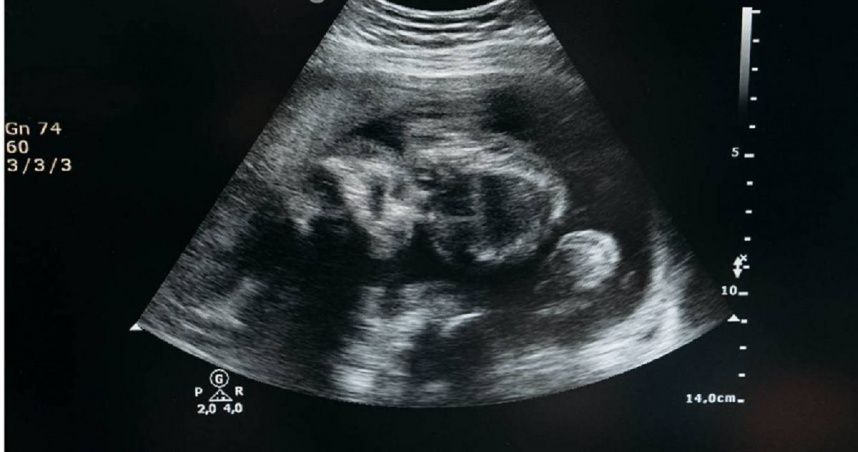

據《ctwant》報導,原PO生完老大後,隔了三年才迎來老二,因為尚未過三個月穩定期,老公為了讓她好好養身體,家事都扛下來做,也不讓原PO上班,「婆婆直接在我面前跟老公說,你老婆是都不能動了嗎?」幾天過去,她開開心心前往醫院準備領媽媽手冊,卻被檢查出胎停,「這下婆婆沒話說了...」